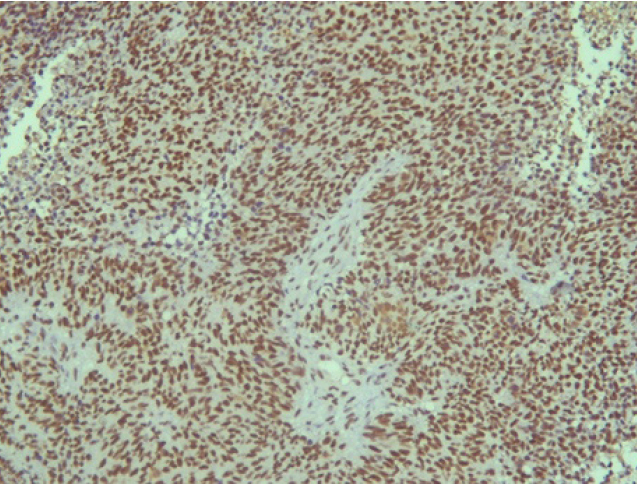

Поэтому при первичном гистологическом исследовании диагноз эстезионейробластомы был установлен только у 6 пациентов (66,6 %), у троих больных (33,4 %) были диагностированы другие формы злокачественного процесса, что не соответствовало клиническим проявлениям. Во всех случаях проводили иммуногистохимическое (ИГХ) исследование. ИГХ-исследование проводили на срезах с парафиновых блоков с использованием антител к Keratin.Pan (AE/AE3), CD45 (Cocktail), Synaptophysin (SP11), ChromograninA (SP12), CD56 (56C04), Ki-67 (30-9), p63 (7JUL)RTU, S100, INI1, CD99 (HO36-1.1). Также выполняли доставку с антителами к EMA (E29), TTF1 (8G7G3/1). В диагностических материалах была отмечена положительная экспрессия Synaptophysin, ChromograninA, CD56, Ki-67 (до 90% ядер), INI1 (рис. 2–6).

Рис. 5. Ki-67 [30-9] (90%) ×200

Эти результаты иммуногистохимического исследования подтверждают наибольшее соответствие иммунофенотипа опухоли – ольфакторной нейробластоме (G3 по Hyams) М9522/33.

В последнее время значительное большинство авторов считают дифференцировку опухоли важнейшим фактором прогноза [7, 10]. Одним из способов определения злокачественности является изучение пролиферативной активности опухолевых клеток – индекс Ki-67 (клон MIB-1) [2, 8].